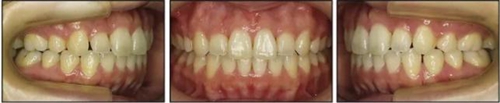

五、治療結(jié)果

治療后數(shù)據(jù)提示治療目標(biāo)達(dá)成。面相結(jié)果提示微笑及側(cè)貌得到改善(圖6)。達(dá)到了安氏I類(lèi)尖牙關(guān)系和安氏II類(lèi)磨牙關(guān)系,形成尖牙保護(hù)合。牙齒中線無(wú)偏斜,達(dá)到理想的覆合覆蓋,Spee曲線得到整平。

治療后全景片提示間隙得到關(guān)閉,除了左下頜第一前磨牙外牙根平行度可,無(wú)明顯骨及牙根吸收。(圖7)

治療后頭側(cè)數(shù)據(jù)提示:無(wú)明顯骨性變化(上頜SNA82.1°,下頜SNB74.9°),上頜前牙得到內(nèi)收,略舌傾,頦部前后位置無(wú)明顯改變,仍未凸面型(圖8,表)。將治療前后圖像重疊后結(jié)果如(圖8及圖9),24月后隨訪結(jié)果見(jiàn)圖10.